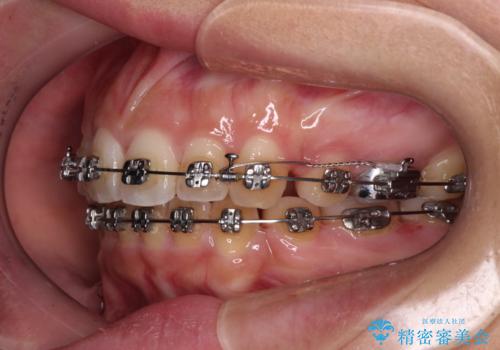

- メタルブラケット

- 3年3ヶ月

- 30回以上

奥歯の噛み合わせは正常に近い状態でしたが、右上の奥歯に突起があったり、上下前歯が非接触であったりしていたため、補助装置を使用して上顎前歯を積極的に引っ込めるように計画しました。

口元の突出感を改善するために上下左右の小臼歯4本を抜歯し、ワイヤー装置によりデコボコを解消しながら口元の突出感も改善していくこととしました。